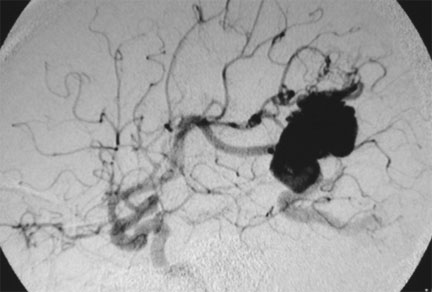

CASO 2 : Embolización combinada con Radiocirugía. Paciente con crisis convulsivas y trastorno del lenguaje. La angiografía demuestra voluminosa MAV localizada en plena área del lenguaje.

Angiografía antes de la embolización

Angiografía 7 años después de la embolización mostrando reducción importante y definitiva del volumen de la MAV, convirtiéndola en blanco óptimo para radiocirugía

Al cabo de 18 meses de la radiocirugía la MAV está curada sin efectos adversos ni secuelas. El paciente continuó su trabajo e incluso estudios de post grado.